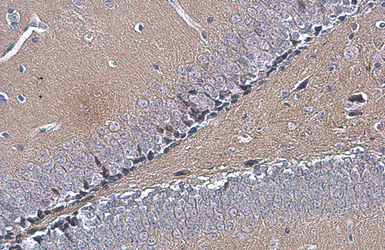

OTUB1 antibody [N1C1] detects OTUB1 protein at cytoplasm by immunohistochemical analysis.

Sample: Paraffin-embedded mouse hippocampus.

OTUB1 stained by OTUB1 antibody [N1C1] (GTX101973) diluted at 1:500.

Antigen Retrieval: Citrate buffer, pH 6.0, 15 min